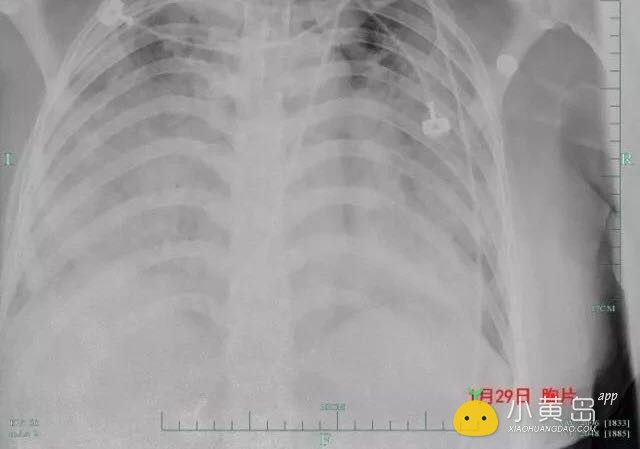

微信图片_20180402140828.jpg

(美琳的肺部近乎“白肺”,情况危急)